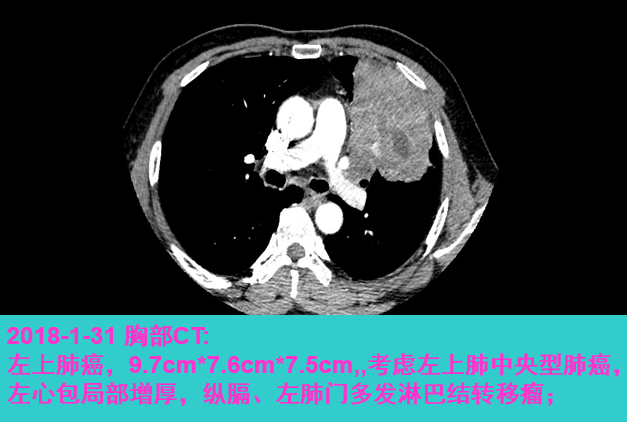

入院后完善相关检查,胸部CT(2018年1月31日,图1):左上肺软组织肿块,大小9.7*7.6*7.5cm,考虑左上肺中央型肺癌并纵膈及左肺门多发淋巴结转移可能性大;心包局部增厚;左肾上腺增粗,不除外转移。腹部+盆腔CT、骨扫描、头部MRI、腹部+颈部超声未见明显异常。

image001.png

图1.患者2018年1月31日胸部CT